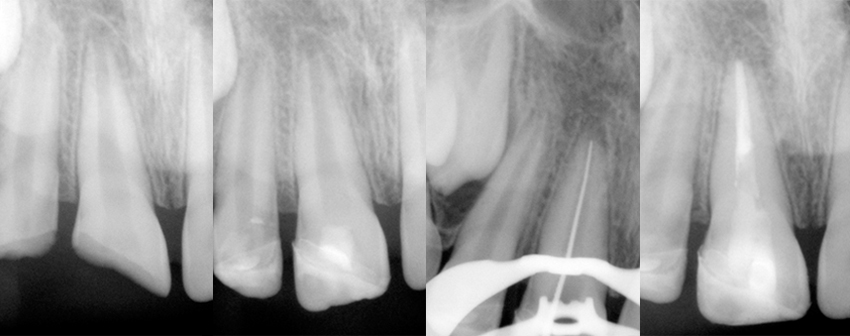

Terapia endodontica complessa

Incisivi laterale e centrale superiori destri fratturati per trauma domestico in bambino di 8 anni.

Il centrale aveva l’apice radicolare non formato e si è proceduto con un incappucciamento diretto per favorire il completamento della formazione dell’apice radicolare (apicogenesi), evitando una difficile chiusura dell’apice (apecificazione), poi il restauro è eseguito utilizzando i frammenti dentali stessi recuperati dai genitori ed infine a distanza di tempo viene effettuata la corretta terapia canalare e la ricostruzione in composito.